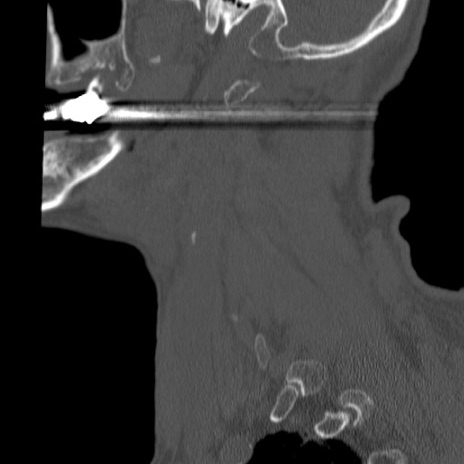

症例46 頚椎CT(矢状断像)

【症例】80歳代男性

【主訴】両側頚部〜上肢のしびれ

【現病歴】昨日、自宅内で転倒、その後より上記症状あり。意識障害なし。

【身体所見】両側上肢のallodynia(熱痛覚過敏)あり。MMTおよびDTRは正確な所見取れず。両上肢の挙上はなんとか可能。

異常所見と診断は?